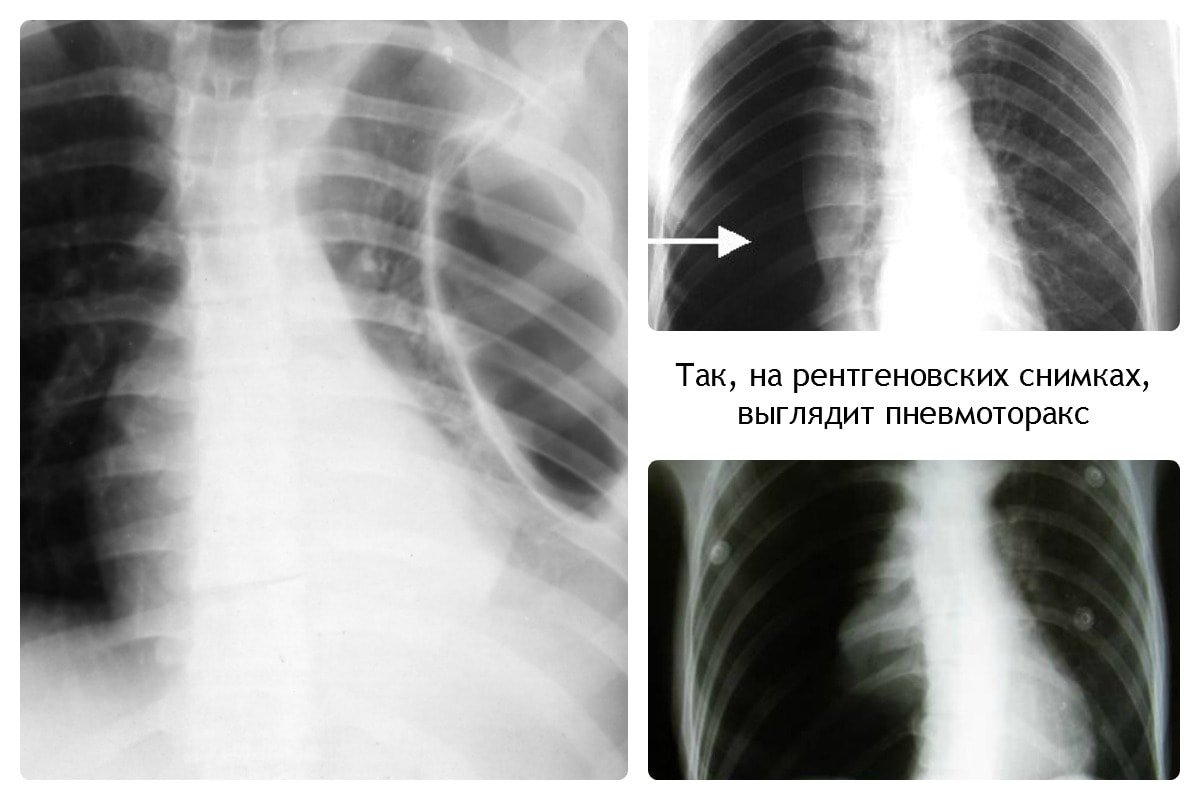

При пневмотораксе присутствует характерный уровень жидкости. На снимке отображается как просветление, лёгочный рисунок не просматривается.

Вирусная пневмония на рентгеновском снимке выглядит следующим образом: